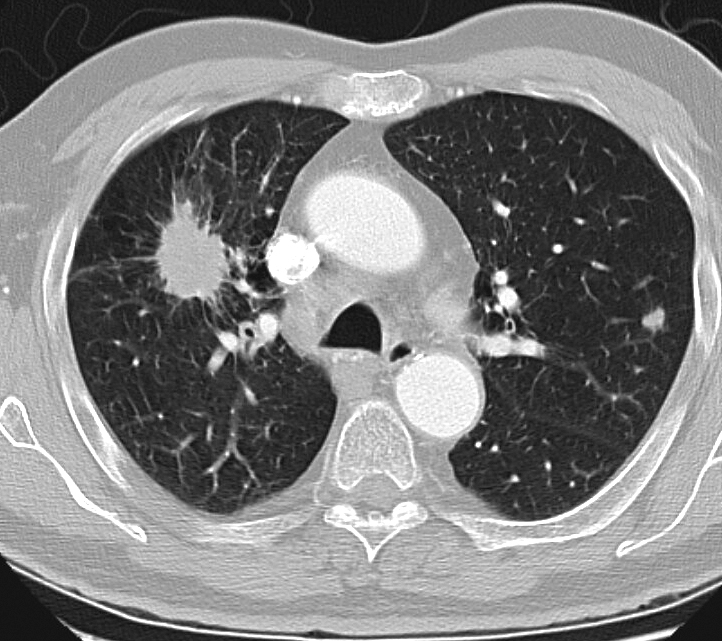

Рентгеновские снимки опухоли Панкоста